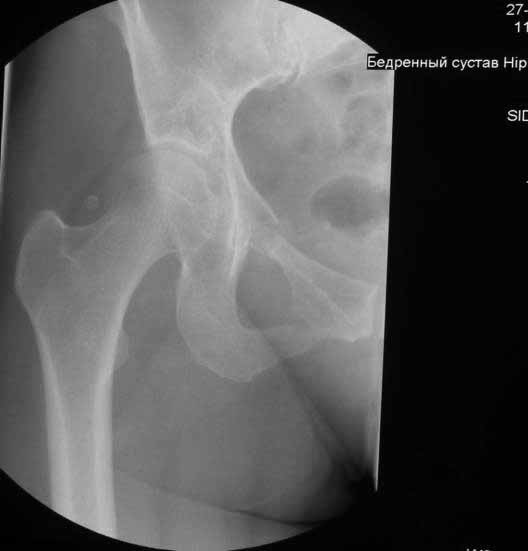

Уважаемые коллеги. Хотелось бы услышать мнения и советы по представляемому случаю. Пациентка 45 лет. Бесцементное эндопротезирование левого тазобедренного сустава 6 лет назад (впадина RM, Mathys, металл-металл, ножка Зульцеровская). За 10 лет до протезирования – коррегирующая остеотомия бедренной кости, которая не срослась в течение года до удаления пластины, а затем срослась в течение 3 месяцев иммобилизации в кокситной повязке. После протезирования получилось наблюдать пациентку почти постоянно, поскольку через 2 года синтезировал ей лодыжки на оперированной стороне, затем, через несколько месяцев удалил фиксаторы, а в 2009г. резецировал мениск на противоположной стороне. Боли все эти годы не беспокоили. Пациентка чуть выше среднего роста, вес тела нормальный. Физические нагрузки переносила хорошо. Работает на 7 этаже без лифта. Год назад экстирпация матки по поводу лейомиомы больших размеров. Несколько месяцев назад появились боли в области левого тазобедренного сустава. При рентгеновском и КТ исследованиях (июль с.г.) – нестабильность тазового компонента. От предложенной замены протеза пациентка на тот момент, слава богу, отказалась. Через какое то время боли в области левого тазобедренного сустава практически полностью прошли, а около 2 месяцев назад появилось ощущение патологической подвижности таза и боли в паху справа, которые через некоторое время уменьшились, а потом снова усилились после значительных физических нагрузок (много ходила по песку на пляже, носила тяжести). Ежедневно принимала диклофенак. На рентгенограммах – переломы правой лонной кости. Сейчас госпитализирована из-за болей в паху справа. Боли слева не беспокоят. На фоне снижения нагрузок в стационаре боли значимо уменьшились. Способна ходить без средств дополнительной опоры.В анализах крови чуть повышены трансаминазы и гамма-ГТ, моча без особенностей.

Вопросы: -правильно ли я расцениваю переломы как стрессовые на фоне неполноценного таза (pelvic insufficiency stress fractures)? -Можно ли так же расценить ситуацию на стороне протеза и, соответственно, не торопиться с ревизией, рассчитывая на вторичную стабилизацию? Уж больно не хочется менять ножку. -Если думать о ревизии, то когда? На представленных снимках тазобедренный сустав до и сразу после операции, затем 2 снимка 2009г., когда ничего не беспокоило, затем КТ 2-х месячной давности и вчерашние рентгенограммы обоих тазобедренных суставов.

Уважаемый Сергей,

Похоже Вы правы,это напоминает перегрузочный перелом, но вопрос о его причине остается открытым, просто ли это избыточная нагрузка на правую половину таза вследствие нестабильности чашки слева и ограничение нагрузки на левую половину, либо это гормональные изменения, приведшие к изменению метаболизма и перелому. Я бы дождался консолидации и поставил вопрос о замене чашки. Молодая женщина, 45 лет, пока еще можно обойтись достаточно простой манипуляцией, если процесс начался, его не остановить, но дальше будет намного сложнее.

Если внимательно посмотреть на рентгеновские снимки, то видно, что пара трения действительно металл-металл.